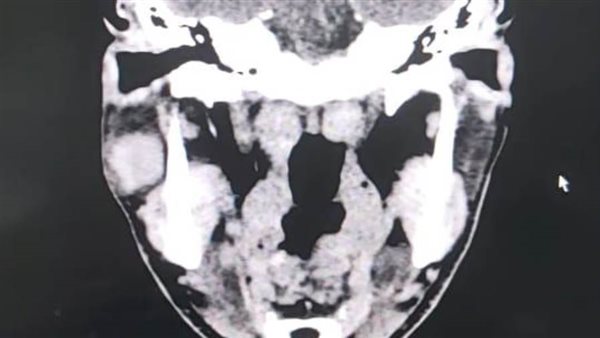

قام قسم جراحة الوجه والفكين بمستشفى ادكو المركزى فى إجراء عملية دقيقة لإزالة ورم من الغدة النكافية "ورم حميد بالغدة النكافيه من الفص السفلي لها" وبفضل الله تم الحفاظ على العصب الوجهي السابع.